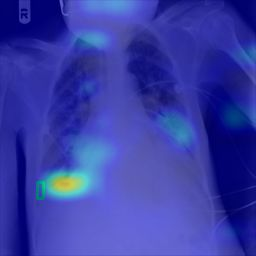

Deployments of artificial intelligence in medical diagnostics mandate not just accuracy and efficacy but also trust, emphasizing the need for explainability in machine decisions. The recent trend in automated medical image diagnostics leans towards the deployment of Transformer-based architectures, credited to their impressive capabilities. Since the self-attention feature of transformers contributes towards identifying crucial regions during the classification process, they enhance the trustability of the methods. However, the complex intricacies of these attention mechanisms may fall short of effectively pinpointing the regions of interest directly influencing AI decisions. Our research endeavors to innovate a unique attention block that underscores the correlation between 'regions' rather than 'pixels'. To address this challenge, we introduce an innovative system grounded in prototype learning, featuring an advanced self-attention mechanism that goes beyond conventional ad-hoc visual explanation techniques by offering comprehensible visual insights. A combined quantitative and qualitative methodological approach was used to demonstrate the effectiveness of the proposed method on the large-scale NIH chest X-ray dataset. Experimental results showed that our proposed method offers a promising direction for explainability, which can lead to the development of more trustable systems, which can facilitate easier and rapid adoption of such technology into routine clinics. The code is available at www.github.com/NUBagcilab/r2r_proto.